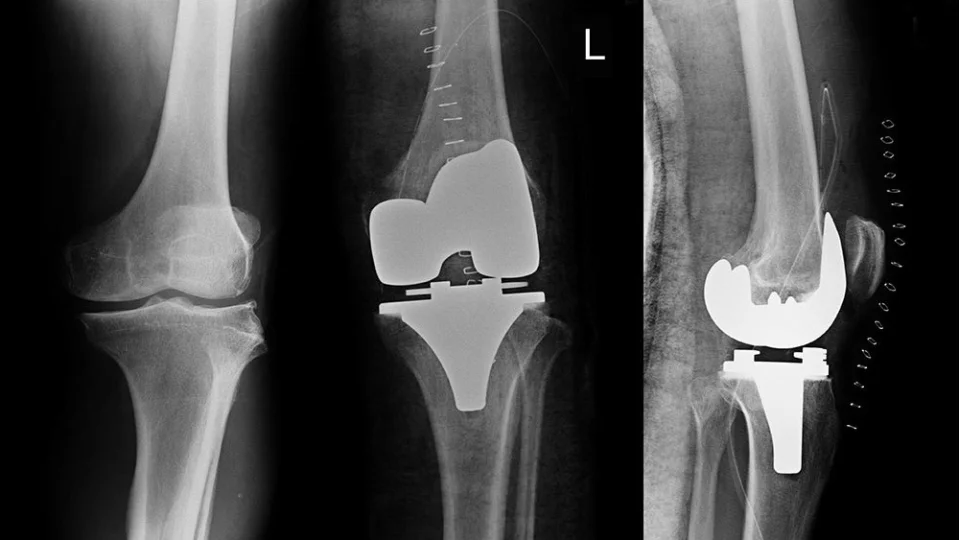

Ekip ayrıca bu yöntemi, gerçek diz protezi ameliyatlarından alınan insan kıkırdağı üzerinde de test etti.

Hatta ciddi şekilde hasar görmüş insan dokusunda bile, bu tedavi hücrelerin sadece birkaç gün içinde yeni, sağlıklı kıkırdak üretmeye başlamasını sağladı.